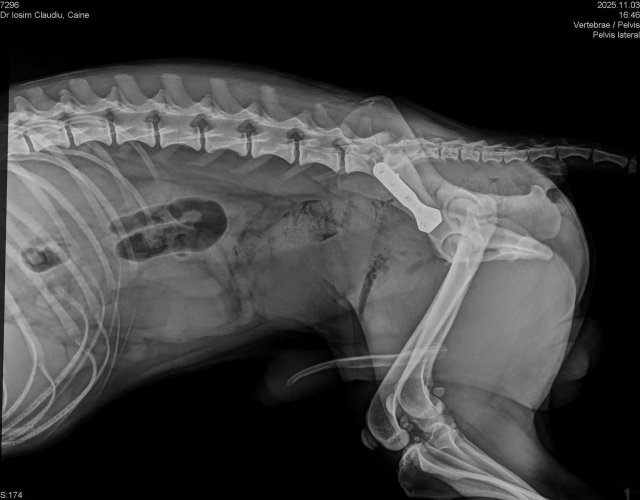

Caine accidentat

O doamna a gasit un caine lovit de masina si l-a tras pe marginea drumului pentru a suna peste tot in cautare de ajutor. Am raspuns pozitiv si am facut totul pentru el. Din pacate nu a putut fi salvat, decedand a doua zi dupa interventia chirurgicala. Foarte probabil din cauza unei embolii pulmonare. Le multumim celor care au donat. Medicul a anulat factura iar banii vor ajuta desigur alte animale de care ne ocupam zilnic.